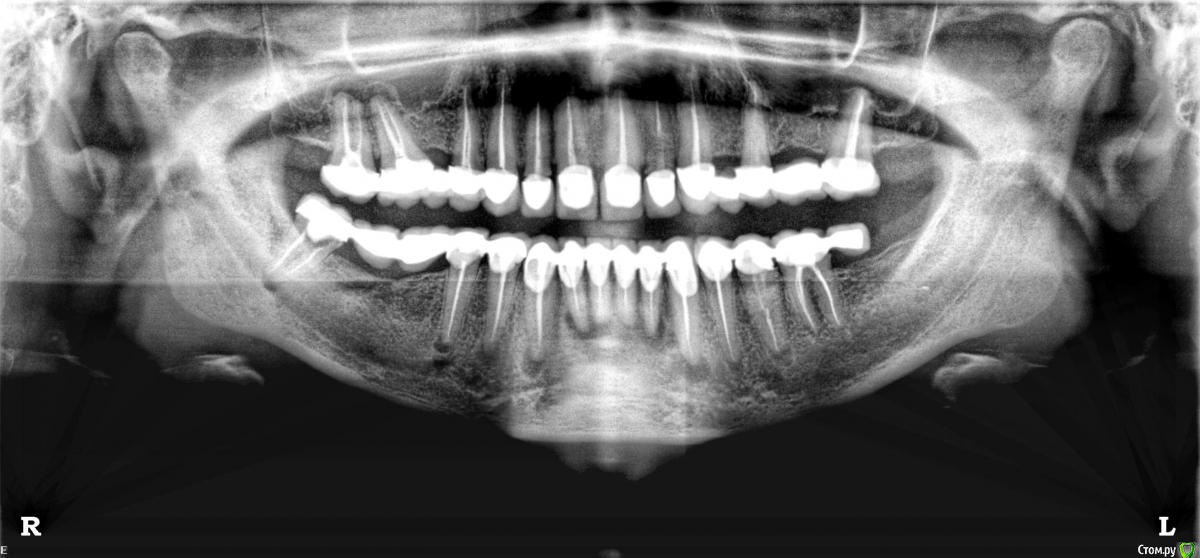

viky Опубликовано 13 марта, 2015 Поделиться Опубликовано 13 марта, 2015 Здравствуйте! В 2012 году делала протезирование. Были проблемы: отлетала коронка, появился свищ, снимок сделать не могла, была в положении. На 8 марта этого года сходила с ума от зубной боли, панорама показала кисты почти под всеми протезированными зубами.Глупость моего протезирования, пожалуйста, не обсуждайте. Подскажите, что сейчас делать? Возможно ли в Москве терапевтическим путем попробовать лечить их?Кисты без сомнений появились в результате плохого протезирования? Заранее благодарна всем ответившим Ссылка на комментарий

red_butler Опубликовано 14 марта, 2015 Поделиться Опубликовано 14 марта, 2015 (изменено) Спасибо, сюда написала, желающих пока нет :-(Скажите, пожалуйста, а с верхними зубами какая ситуация, тоже кисты? (Мнения врачей расходятся)наверху точно перелечивать 1.7 1.6, остальные уточнять прицельными снимками или Кт Изменено 14 марта, 2015 пользователем red_butler Ссылка на комментарий

DmitrySH Опубликовано 14 марта, 2015 Поделиться Опубликовано 14 марта, 2015 Нет, тут не "или" КТ, а обязательно КТ Ссылка на комментарий